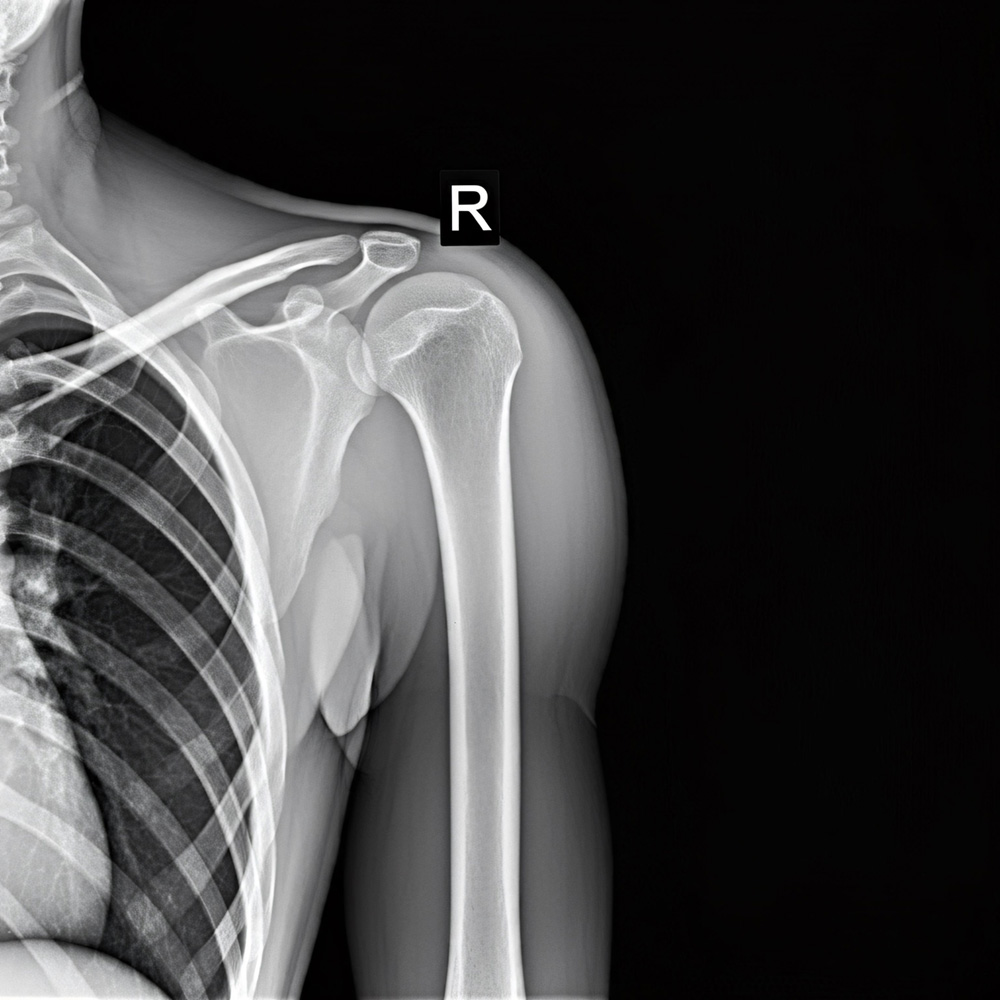

Das klassische Röntgenverfahren ist seit Jahrzehnten ein wichtiger Bestandteil der medizinischen Bildgebung. Besonders bei Knochenbrüchen, Gelenkveränderungen, Lungen- und Brustkorbaufnahmen sowie Arhtrose liefert es schnelle und zuverlässige Ergebnisse.

Das Röntgen zählt zu den schnellsten und am häufigsten eingesetzten Untersuchungsverfahren. Innerhalb weniger Minuten liegen die Aufnahmen vor, sodass eine Diagnose zügig gestellt werden kann. Dank moderner Technik erfolgt die Untersuchung mit einer möglichst geringen Strahlendosis bei gleichzeitig hoher Bildqualität.

Röntgen wird vor allem zur Abklärung von Knochenbrüchen, Gelenkveränderungen, Lungen- und Brustkorbaufnahmen oder Bauchübersichtsaufnahmen eingesetzt. Es ist ein schnelles, bewährtes Verfahren zur Ersteinschätzung vieler Krankheitsbilder.